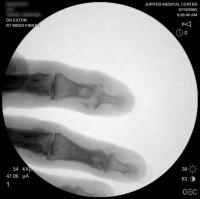

Second case.

This patient had previous experience with both DIP fusion and PIP arthroplasty.

Ring finger DIP joint of the opposite hand.

Xrays one year out.